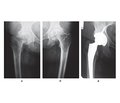

Коломаченко В.І. (1, 2), Одинець І.Ю. (1), Гавриков О.Є. (1, 2), Купін В.І. (2)

(1) - Харківський національний медичний університет, м. Харків, Україна

(2) - Харківська обласна клінічна травматологічна лікарня, м. Харків, Україна

Журнал «Медицина неотложных состояний» Том 21, №6, 2025